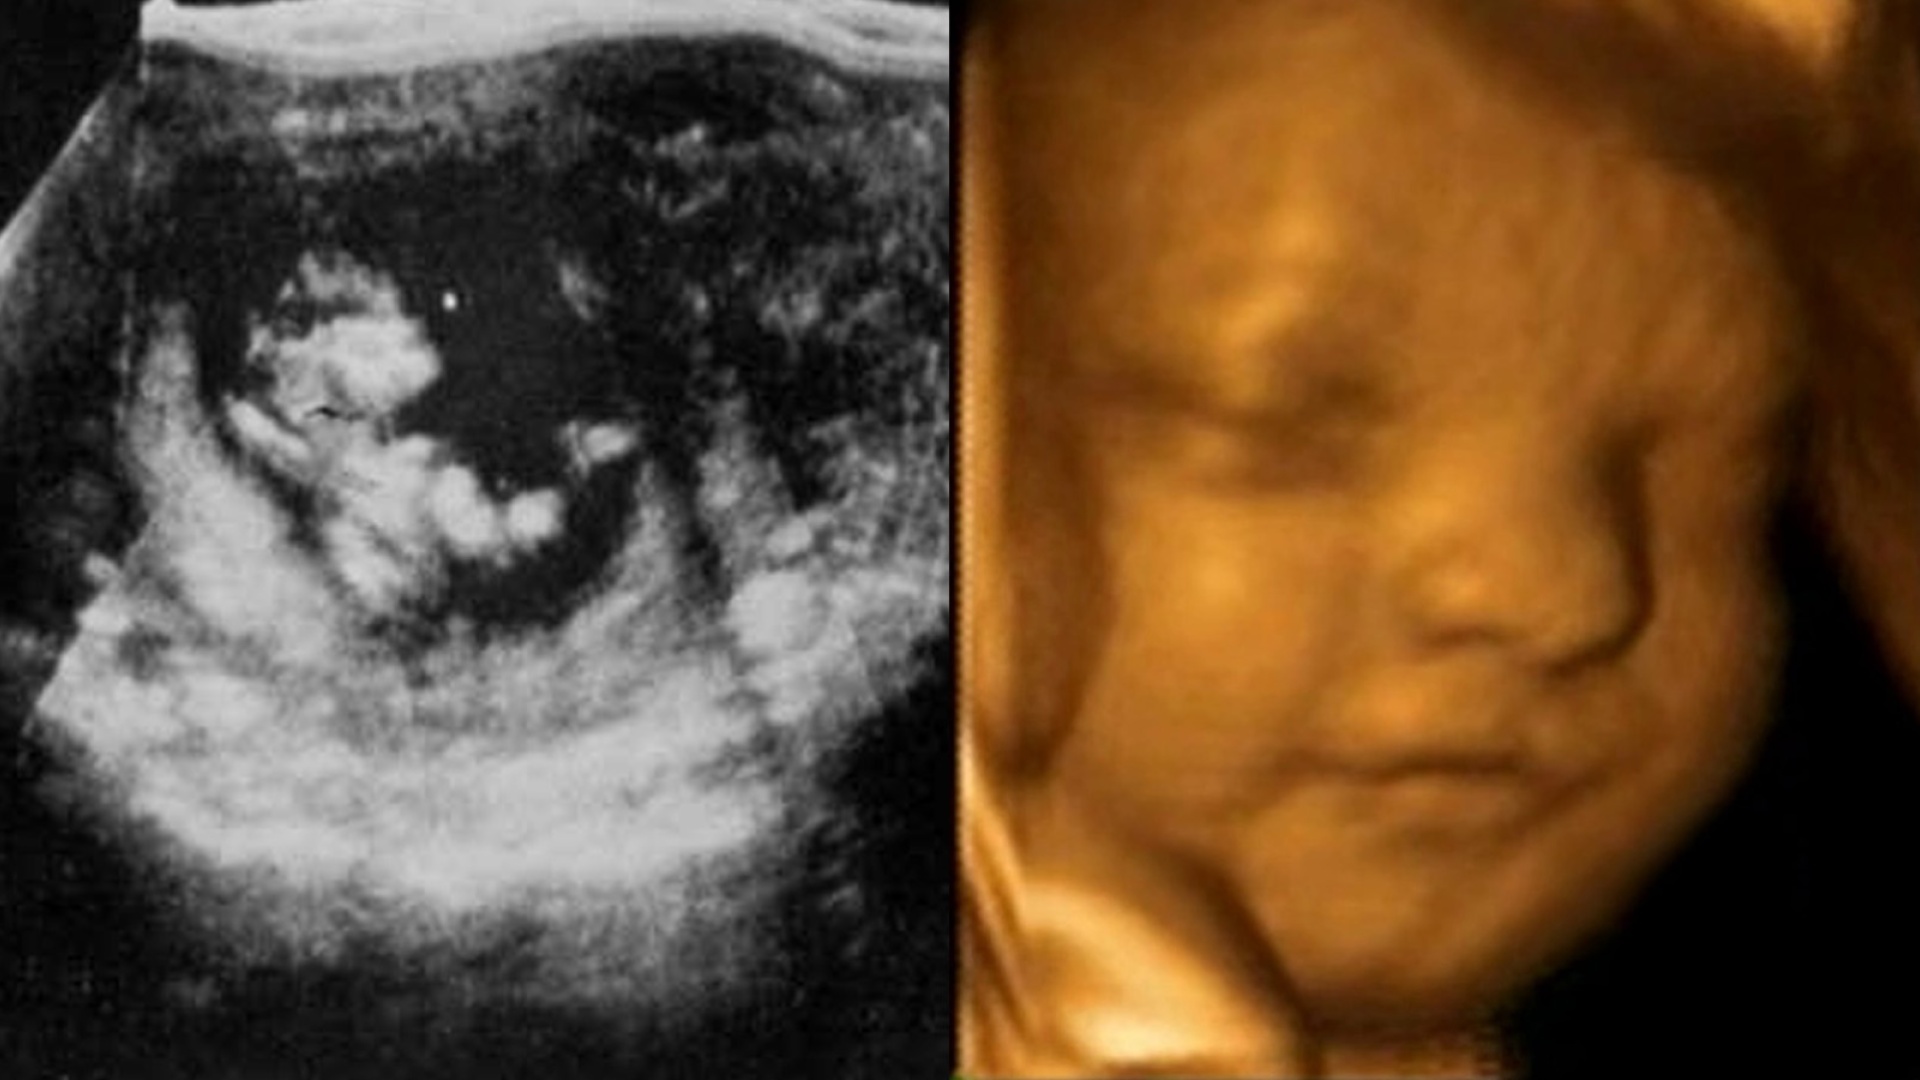

Lancetin artikkelin julkaisun jälkeen ultraäänen käyttö levisi erittäin nopeasti ja siitä tuli hyvin pian normaali operaatio. Vuosien varrella tekniikka on luonnollisesti parantunut ja tullut perusmuodossaankin hyvin tarkaksi, helpoksi ja tehokkaaksi. Lisäksi nyt käytössä on 3D-ultraäänilaitteistoja, joiden avulla esimerkiksi kohdussa olevasta lapsesta saa kolmiulotteiselta näyttäviä kuvia.

Yllä olevassa kuvassa on vasemmalla eräs ensimmäisistä ultraäänikuvista ja oikealla tällainen 3D-kuva. Näiden kuvien välissä on siis 58 vuotta kestänyt tekniikan kehitys.